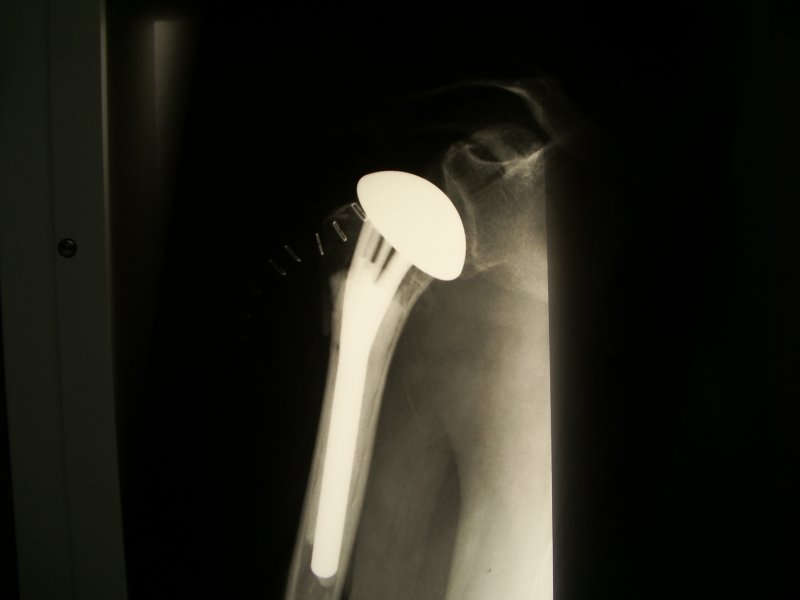

Złamanie główki kości ramiennej z całkowita destrukcja, która uniemożliwila rekonstrukcję i spowodowała konieczność implantacji endoprotezy. Przy zachowanych przyczepach mieśni obręczy kończyny górnej została zastosowana standartowa endoproteza.

Zdjęcie endoprotezy po złamaniu pokazanym na powyższym zdjeciu